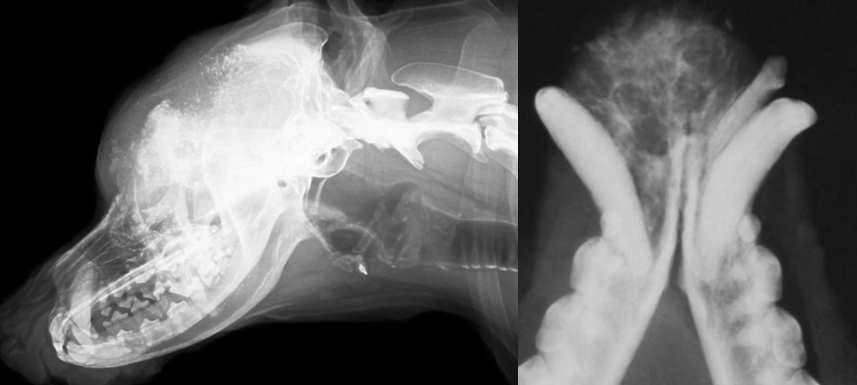

20

Q

identify pathology

A

left image: Fracture of retroauricular processus

right: TMJ dysplasia